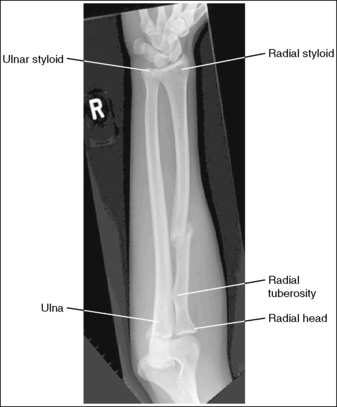

The distal and proximal forearm is positioned in an AP projection. The radial styloid is demonstrated in profile laterally, and superimposition of the metacarpal bases and of the radius and ulna is minimal.

The ulnar styloid is projected distally to the midline of the ulnar head.

The proximal forearm is positioned in an AP projection. The radial head is superimposed over the lateral aspect of the proximal ulna by approximately 0.25 inch (0.6 cm). If included on the IR, the medial and lateral humeral epicondyles are demonstrated in profile at the extreme medial and lateral edges of the distal humerus.

The radial tuberosity is demonstrated in profile medially, and the radius and ulna appear parallel.